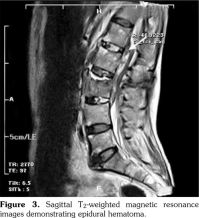

A 61-year-old man was admitted to the department of neurosurgery with bilateral lower extremity weakness which had begun suddenly. The patient had a history of spontaneous falls at home on the same day. He soon developed back pain and weakness in his lower extremities. Magnetic resonance imaging (MRI) of the lumbar spine revealed L2 vertebral fracture and epidural hematoma extending from L2 to L4. The patient underwent decompression surgery for the epidural hematoma. After the surgery, the patient was consulted in our clinic to establish a rehabilitation program. There was a minor trauma in his history two weeks ago, and an ischemic stroke two years ago. The patient reported neck and back pain ongoing for many years, and morning stiffness lasting for 30 minutes. There was no history of night pain, arthritis, skin lesions or inflammatory bowel disease. Upper limb motor strength was normal. Lower limb motor strength examination revealed that bilateral hip flexor and knee extensor strength was 3/5, ankle dorsiflexor strength was 4/5, bilateral toe dorsiflexor strength was 3/5, extensor digitorum brevis muscle strength was 3/5, and ankle plantar flexor strength was 5/5. Sensorial examination was normal. Hoffman, Achilles clonus, and Babinski signs were positive bilaterally. There was no urinary or bowel incontinence. Lumbosacral and sacroiliac joint radiographies were compatible with bilateral grade IV sacroiliitis, syndesmophytes, squared vertebral bodies, and “bamboo spine” formation. Furthermore, radiography revealed anteriorposterior longitudinal ligament calcification and scoliosis (Figure 1, 2).